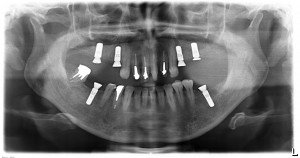

この方は、上下左右にインプラントが必要でしたが、今日の4回目のオペで終了しました。

あとは、2か月後には全体の補綴作業に移っていきます。